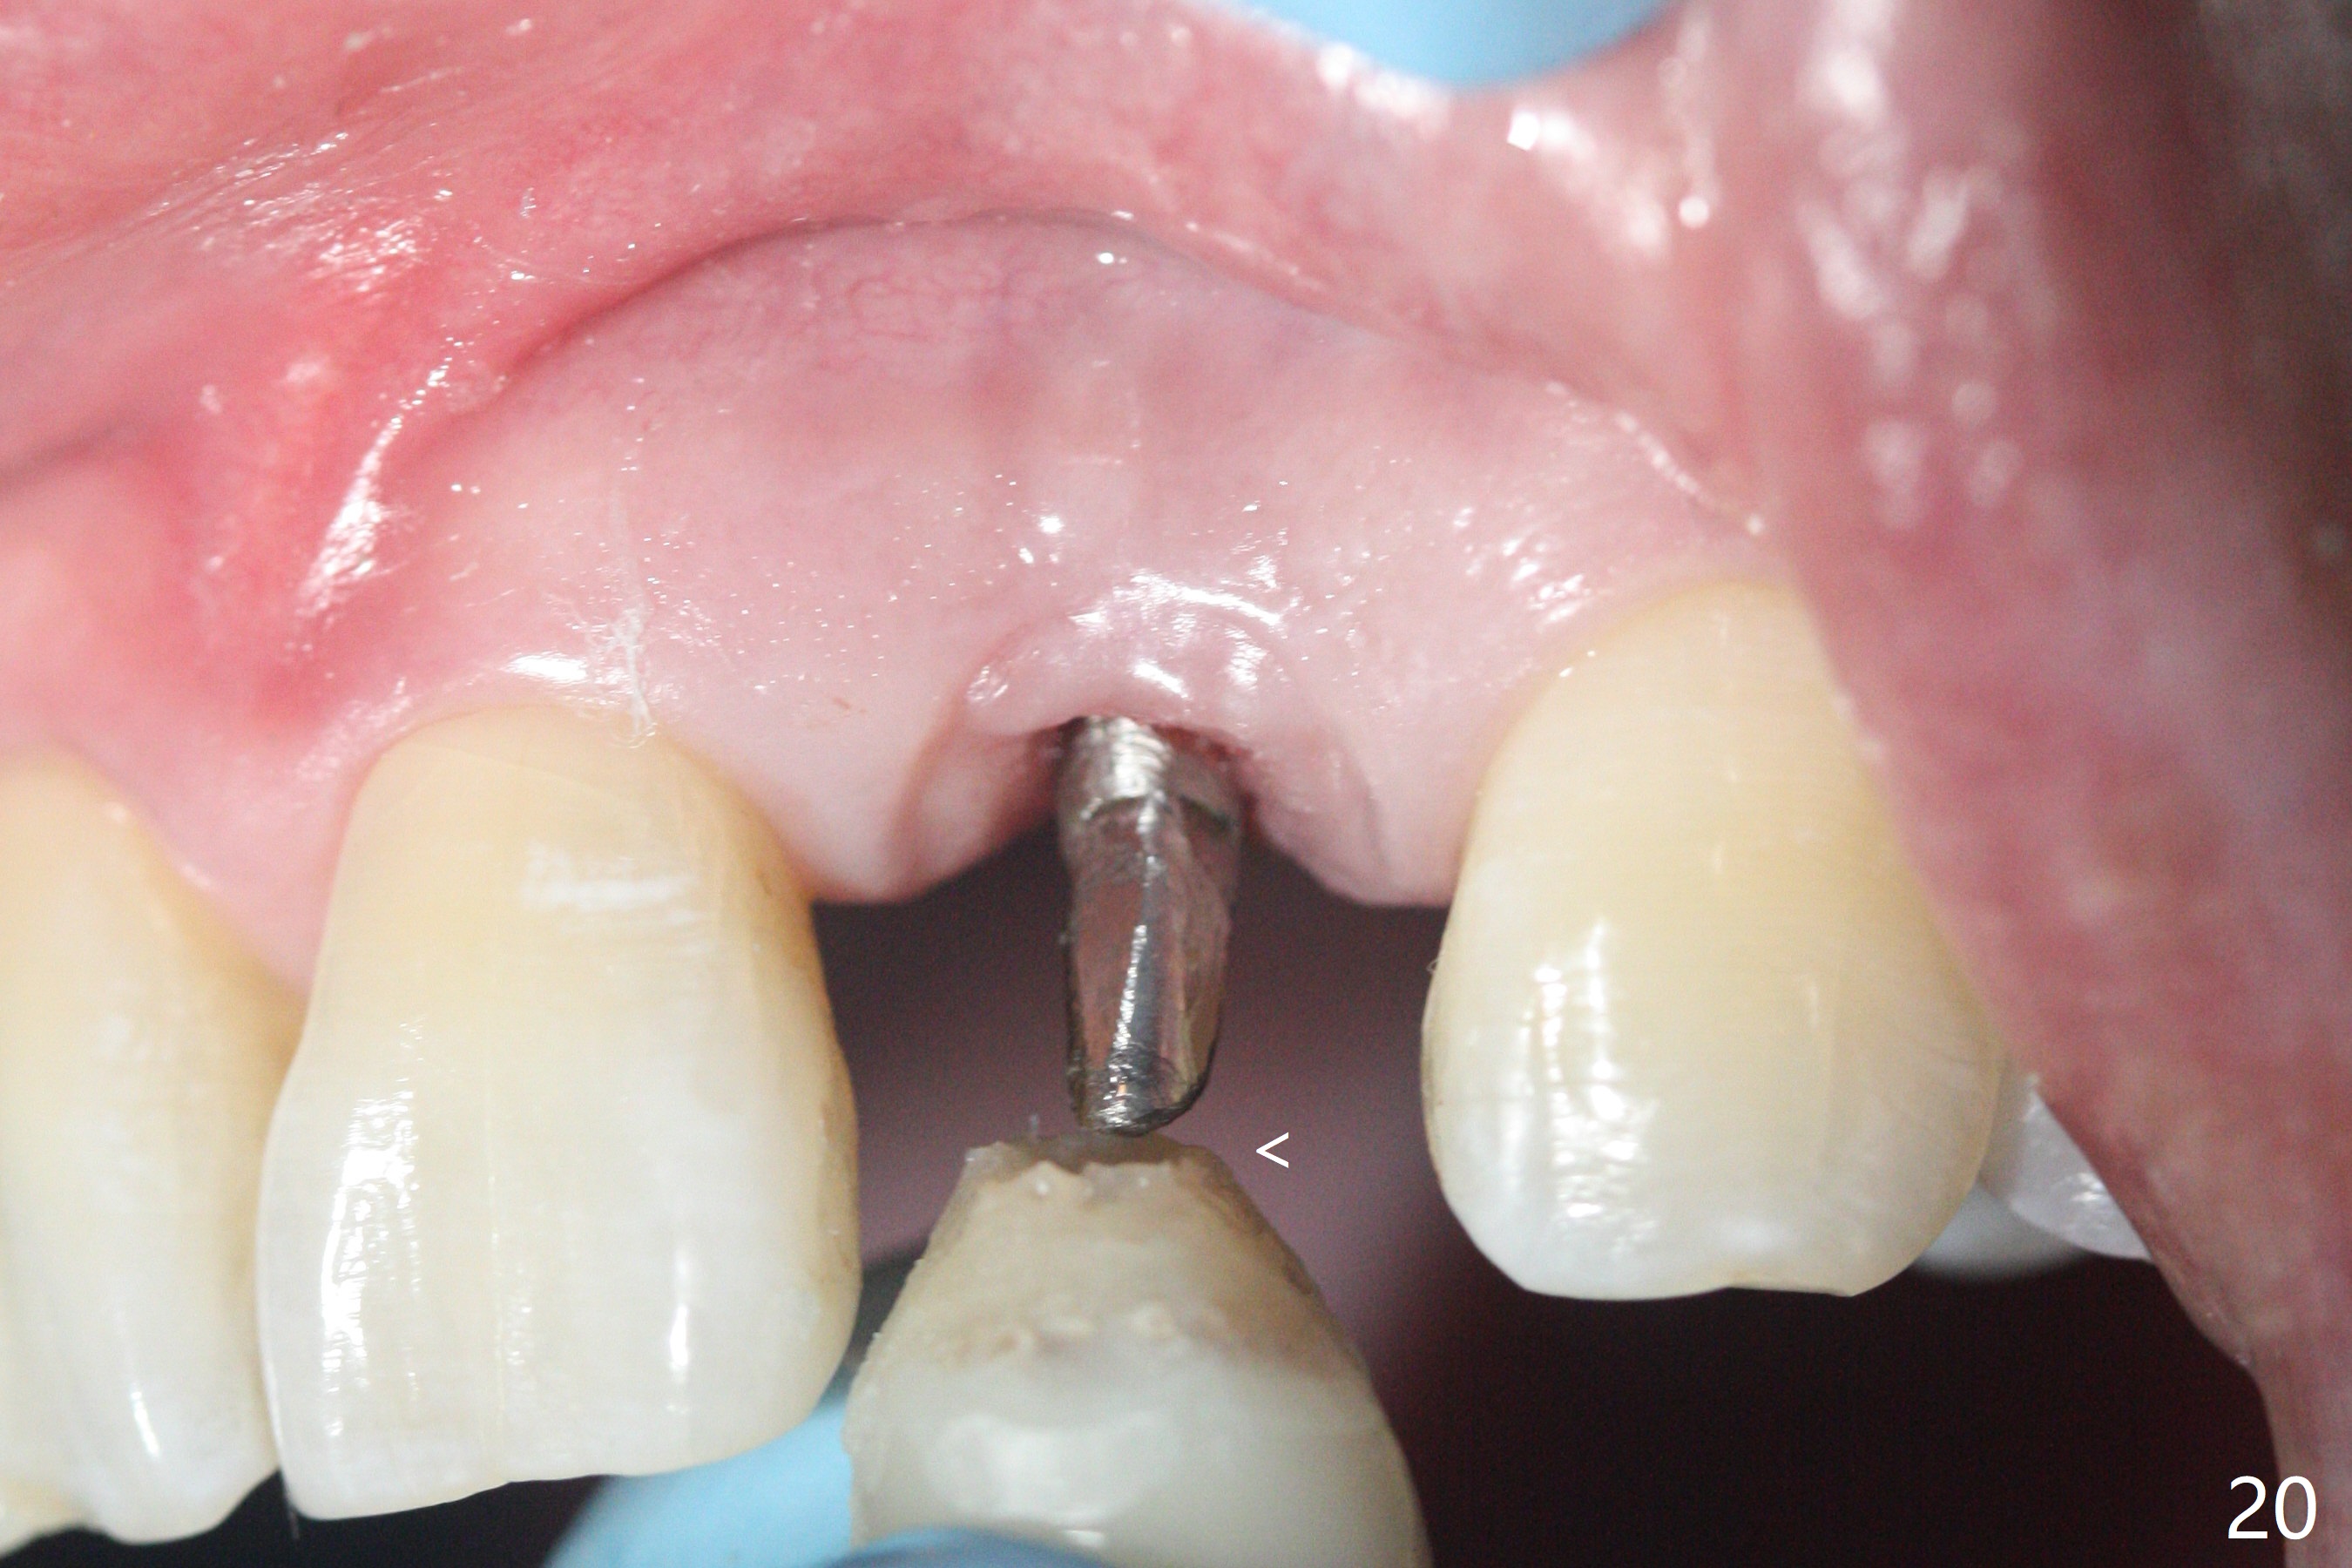

病人回来带来瘘道(图一),不过不会增加难度,病牙去除,它便自动消失。尽管颊侧骨壁完全失去,颊侧牙龈仍丰满(图二),为什么呢?第一,因为粗大牙根存在,第二两旁牙齿,牙槽骨撑着帐篷(侧切牙颊侧牙龈),第三,牙冠。为了防止术后牙龈塌陷,尽量不切开,即刻放置植体(牙根);由于前牙缘故,这次植体不能很大,所以植骨必须过度(over grafting),最后即刻制作临时牙冠,撑住牙龈。这就是所谓每个人进入角色。这个牙根有一种先天性畸形:dens in dent (图三(腭侧观):箭头)。尽管腭侧牙根畸形,腭侧骨壁吸收临床上并不严重,所以钻洞仍偏腭侧。当预定最后钻头还在钻洞时,填入大量粘性骨块(图四:*),细长植体还没有完全卡入鼻底(图五),最后好像可以(图六,七)。植体,骨粉入位(图八),最后临时牙冠出场(图九)。尽管植体小,术后一周临时牙冠仍然可以维持牙龈原有形状(emergency profile,图十:箭头(*:树脂强化牙冠固定))。图十一以不同角度显示瘘道缩小。术后三周取出有些松动的临时牙冠,骨粉虽然还没有被肉芽组织整合,但是显得正常,周围牙龈健康(图十二)。术后4个月牙龈形态正常(图十三),没有触痛;颊侧骨板轻度凹陷(图十四);骨粉仍在原位(图十五)。术后7个月骨粉仍在原位(图十五,十六,但是冠部密度减低(可能骨粉流失,需要牙周或者树脂敷料保护)),没有螺纹暴露。但是牙冠边缘暴露,说明牙龈收缩(图十七,与图十三对比),颊侧骨板仍塌陷(图十八)。插入龈线取得多个目的:修整基台边缘,取模,颊侧牙龈推向颊侧,有利于即将衬里牙冠龈缘进入龈下(图十九)。取模后牙冠边缘(图二十:<)衬里,然后修整,变窄,以便插入龈下,促进颊侧牙龈下降(图二十一,二十二)。术后8个月牙冠粘固前牙龈健康(图二十七,八),牙冠(图二十九)固位后,病人满意(图三十),咬合调整(图三十一),注意腭侧粘固粉流出通道(<)。